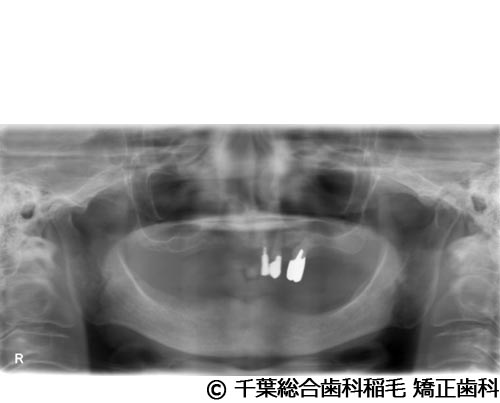

【症例5】All-on-6(オールオン6)

- 治療前

- 治療後

- 治療名

- All-on-6(オールオン6)

- 費用

- 7,500,000円(税込)

- 期間

- 10ヵ月

治療内容

-

患者様の症状

入れ歯が合わなくなり、お食事も満足にできないとご来院されました。

治療法

ご相談の結果、上顎はインプラントを6本、下顎は7本埋入し、All-on-6(オールオン6)という固定式のインプラント治療を行いました。

治療結果

入れ歯が動いてしまう煩わしさがなくなり、よく噛めるようになったと仰っています。

※治療結果は患者様によって個人差があります。